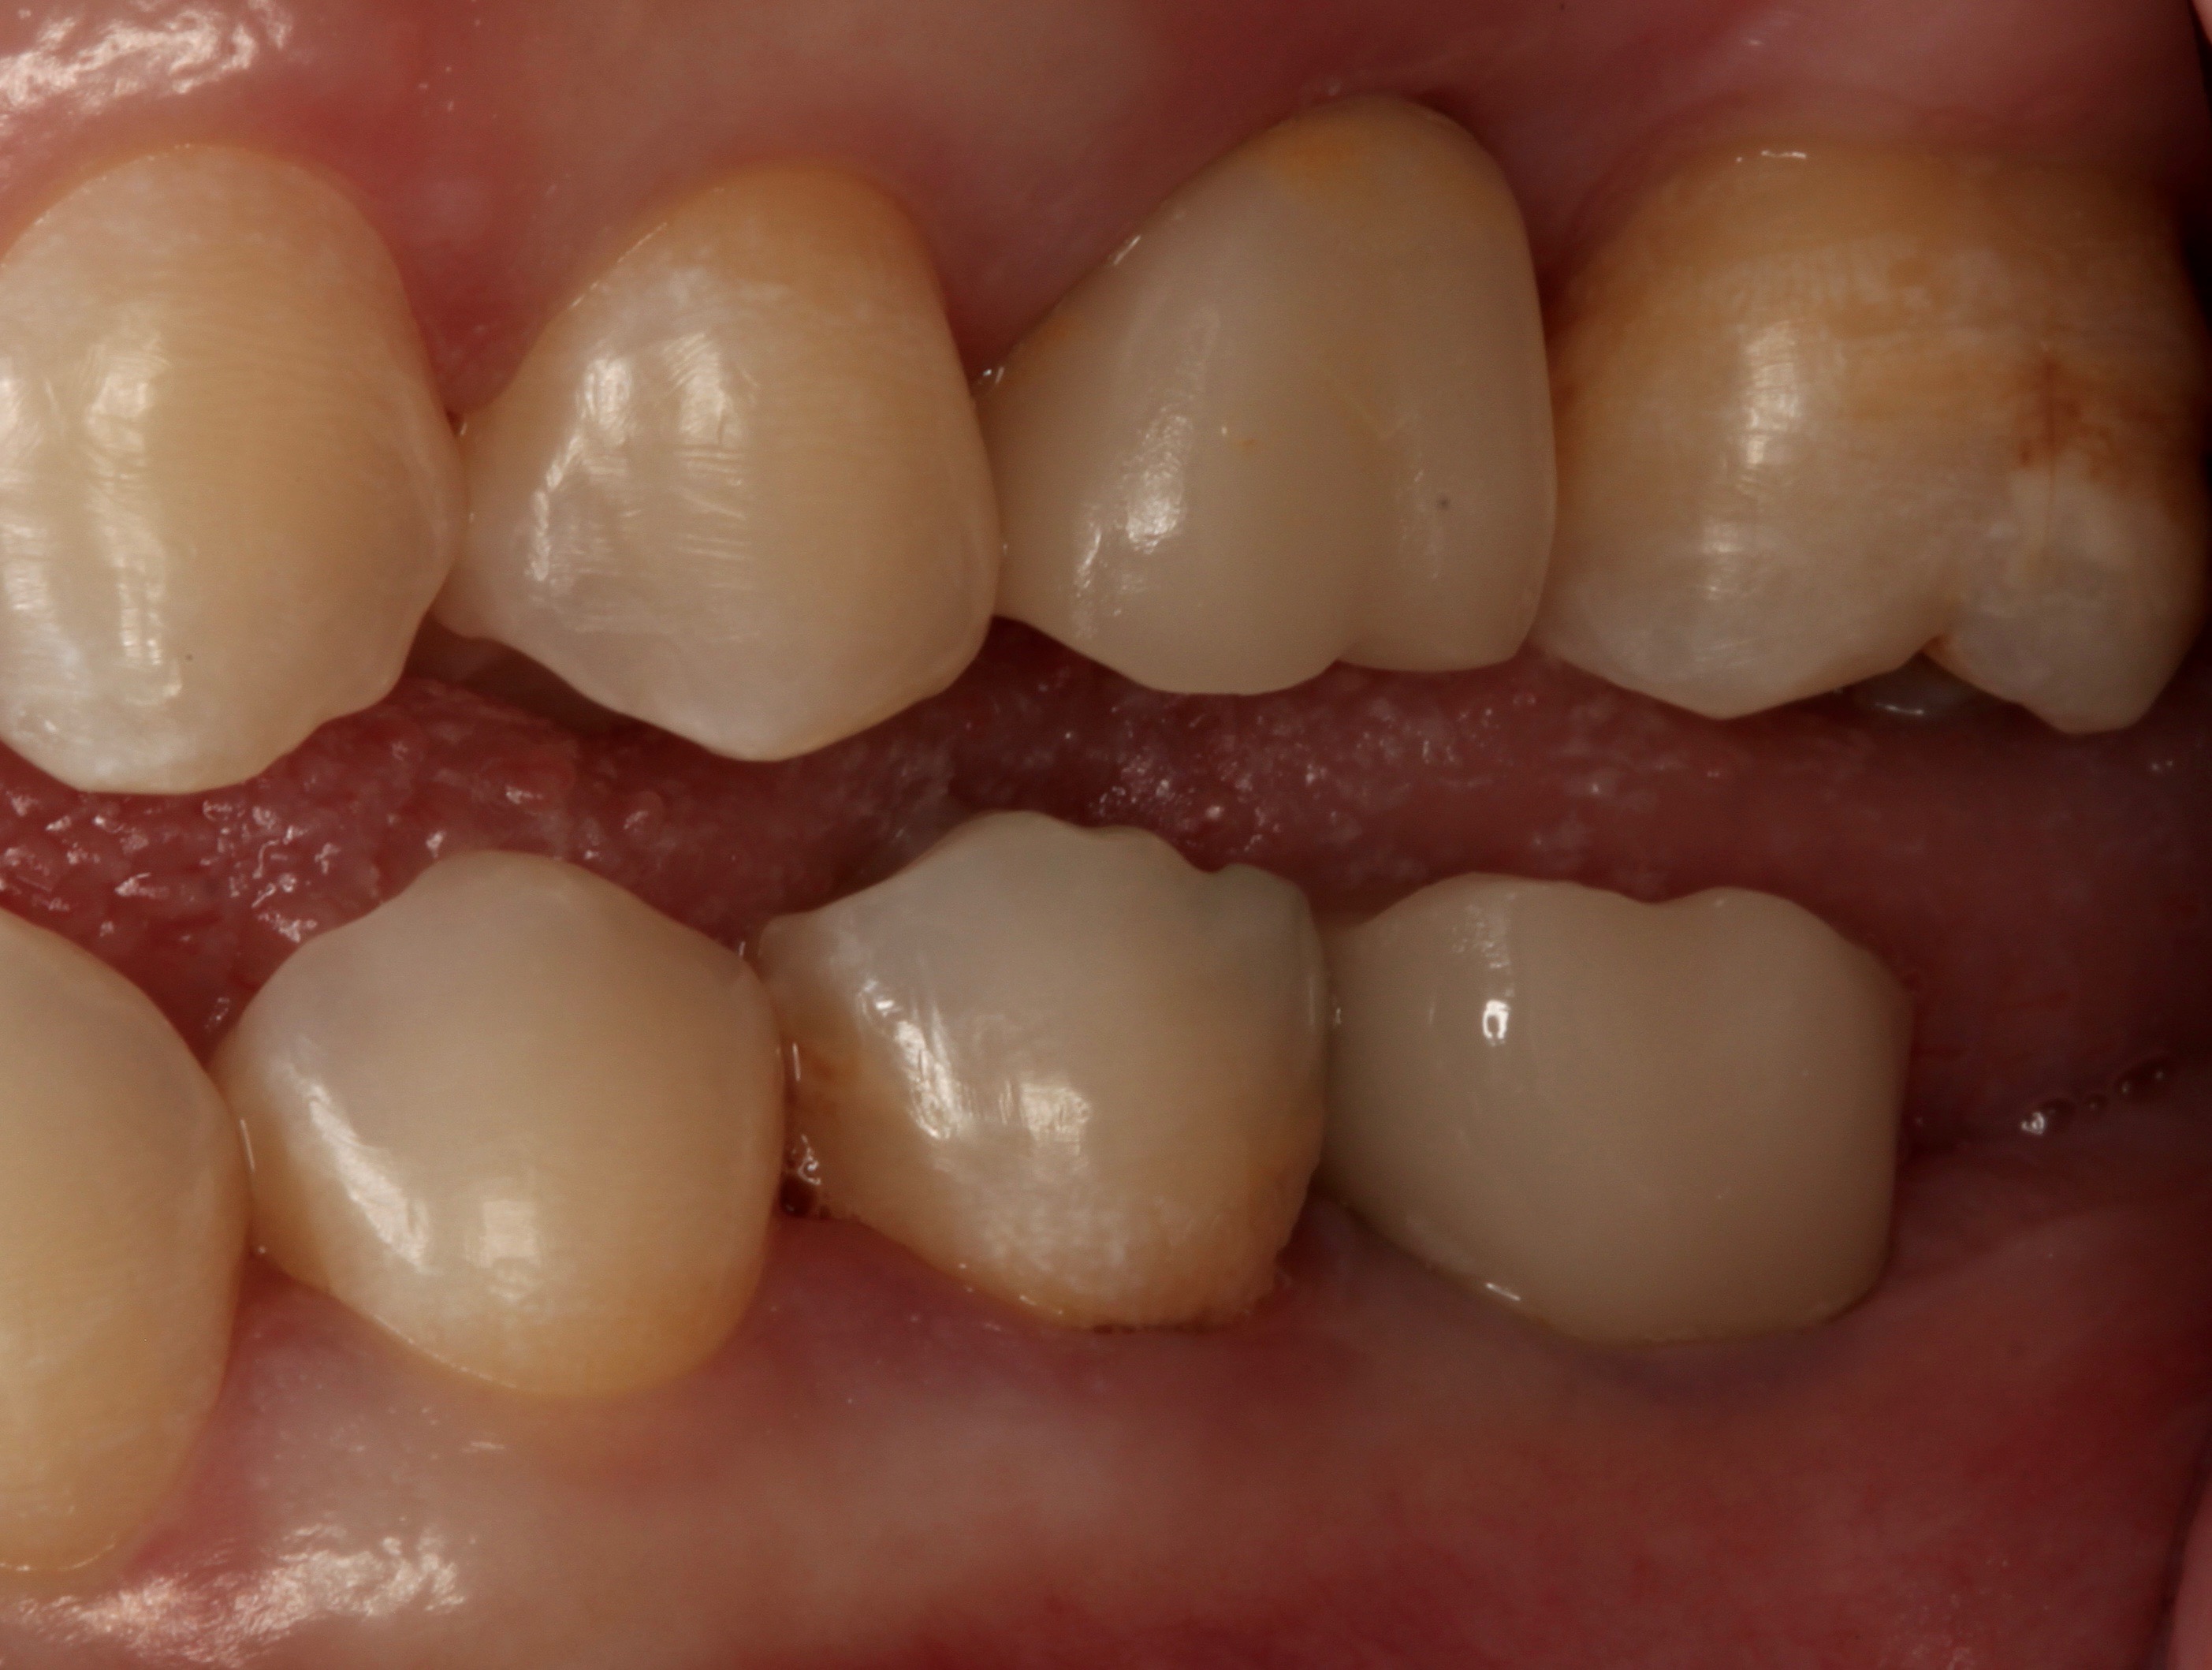

Digital technology is not only great for diagnosis and treatment planning, it also allows that plan to be easily integrated into the restorative workflow. This is a distinct advantage over conventional workflows, especially in esthetic cases when it is critical to meet patient expectations. An illustration of this is a patient presenting with a desire to address his chipped maxillary incisors to make them more esthetic (Figure 1). Using digital photography, a retracted photograph of the patient's teeth was imported into smile-design software, which provided a quick and simple means of establishing a symmetrical restorative design for the patient (Figure 2). Within the same software, the proposed restorations were then overlaid on a full-face smiling photograph (Figure 3), and the patient was able to compare before-and-after photographs (Figure 4). The patient approved of the proposal, which was then imported into CAD software to facilitate fabrication of the final restorations based on the smile-design proposal (Figure 5).

Fig 1. Retracted preoperative view of chipped maxillary incisors.

Figure 1